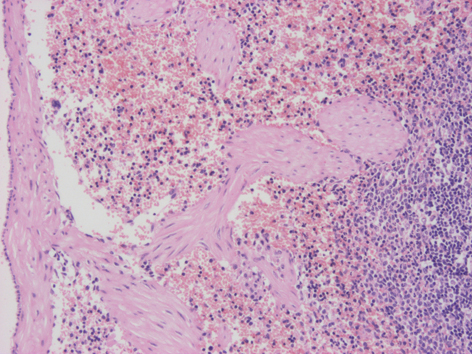

Histológicamente tiene una cápsula (c) fina de tejido conjuntivo que emite trabéculas (t) hacia el interior. En el parénquima se distinguen dos zonas, la pulpa blanca y la pulpa roja. La pulpa blanca es basófila y rica en linfocitos (folículos esplénicos) que se disponen alrededor de arteria corpuscular, la arteriola centrofolicular esplénica (*). La pulpa roja, está integrada por senos vasculares de diversos tamaños, los pequeños drenan en los mayores, y están tapizados por células endoteliales. Estos senos están llenos de células sanguíneas.

Detalle de la pulpa roja